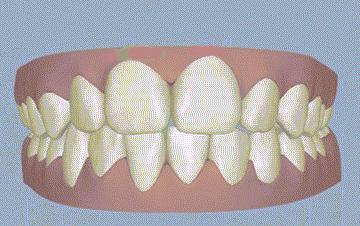

2、深覆合

像下面这样,在牙齿闭合时,上牙把下牙给盖住,下牙只是露出很少一部分就是深覆合。如果有深覆合的情况,要么是因为上牙槽骨发育过度,要么是下牙槽骨发育不足导致的。

深覆合会导致我们的下巴从正面看起来很短,侧面后缩。这种情况的改善方法比较简单常见,也就是去做正畸,不过得花个1~2年的时间(如果骨性问题也突出,可以联合正颌手术矫正)。